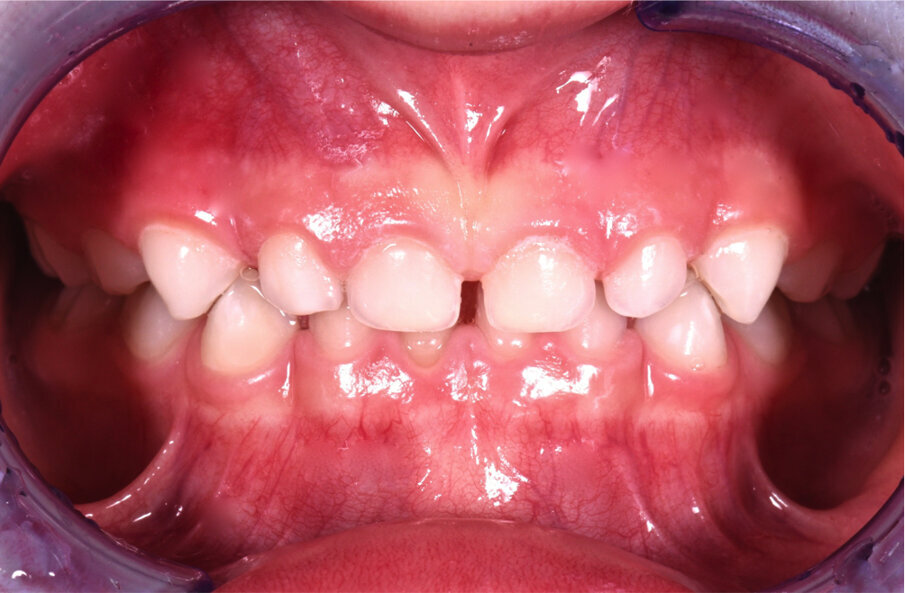

Caso 2 Paziente di anni 4, malocclusione dentale di III Classe, morso crociato monolaterale dx. La paziente viene trattata con dispositivo Amcop TC 2, il quale indossato tutte le notti e 1 ora di pomeriggio in 8 mesi risolve la malocclusione ripristinando il corretto rapporto occlusale; durante la terapia si riscontra un netto miglioramento della respirazione nasale e quindi il ripristino delle normali funzioni respiratorie. Il dispositivo, nei mesi successivi, viene indossato dalla paziente solo la notte per stabilizzare il caso e per guidare la crescita nel miglior modo possibile; all’età di 6 anni la paziente viene sottoposta a check-up ortodontico completo e quindi a panoramica e teleradiografia per poter analizzare anche la previsione di crescita e stabilire un eventuale step elastodontico (Figg. 15-23).

Fig. 15

Fig. 16

Fig. 17

Fig. 18

Fig. 19

Fig. 20

Fig. 21

Fig. 22

Fig. 23